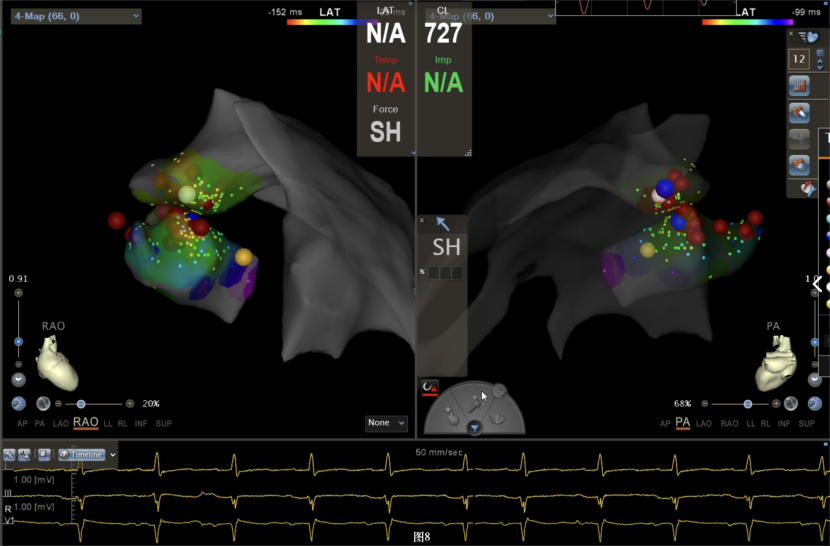

即穿刺股静脉,将消融大头送至冠状窦内,在GCV远端对应位置标测到最早点(图5绿色点)领先体表27ms,消融后早搏未能消失,周明礼评估起源点偏心外膜,能量依旧不能穿透损伤到起源点,内膜消融基本无效后,果断选择难度系数最为复杂的干性心包穿刺心外膜消融。在导丝的指引下,将消融大头送至心包层(图6),于外膜标测到靶点(图7黄色点)电位领先体表31ms,单极电位无r波且有顿挫,ssummit外膜离冠状动脉较近,比较危险,保证安全,进行了冠脉造影(图7),显示距离LAD和LCx有一定距离,相对安全,随即放电,2s室早消失,10s患者出现心率变慢,该区域走形迷走神经节,消融导致心率减慢,随后保证心率正常的情况下,消融够60s,随后观察半小时,早搏没有恢复,手术成功(图8)。经过不懈的努力,患者恢复了窦率,心脏功能也逐渐恢复正常,手术取得了圆满成功。